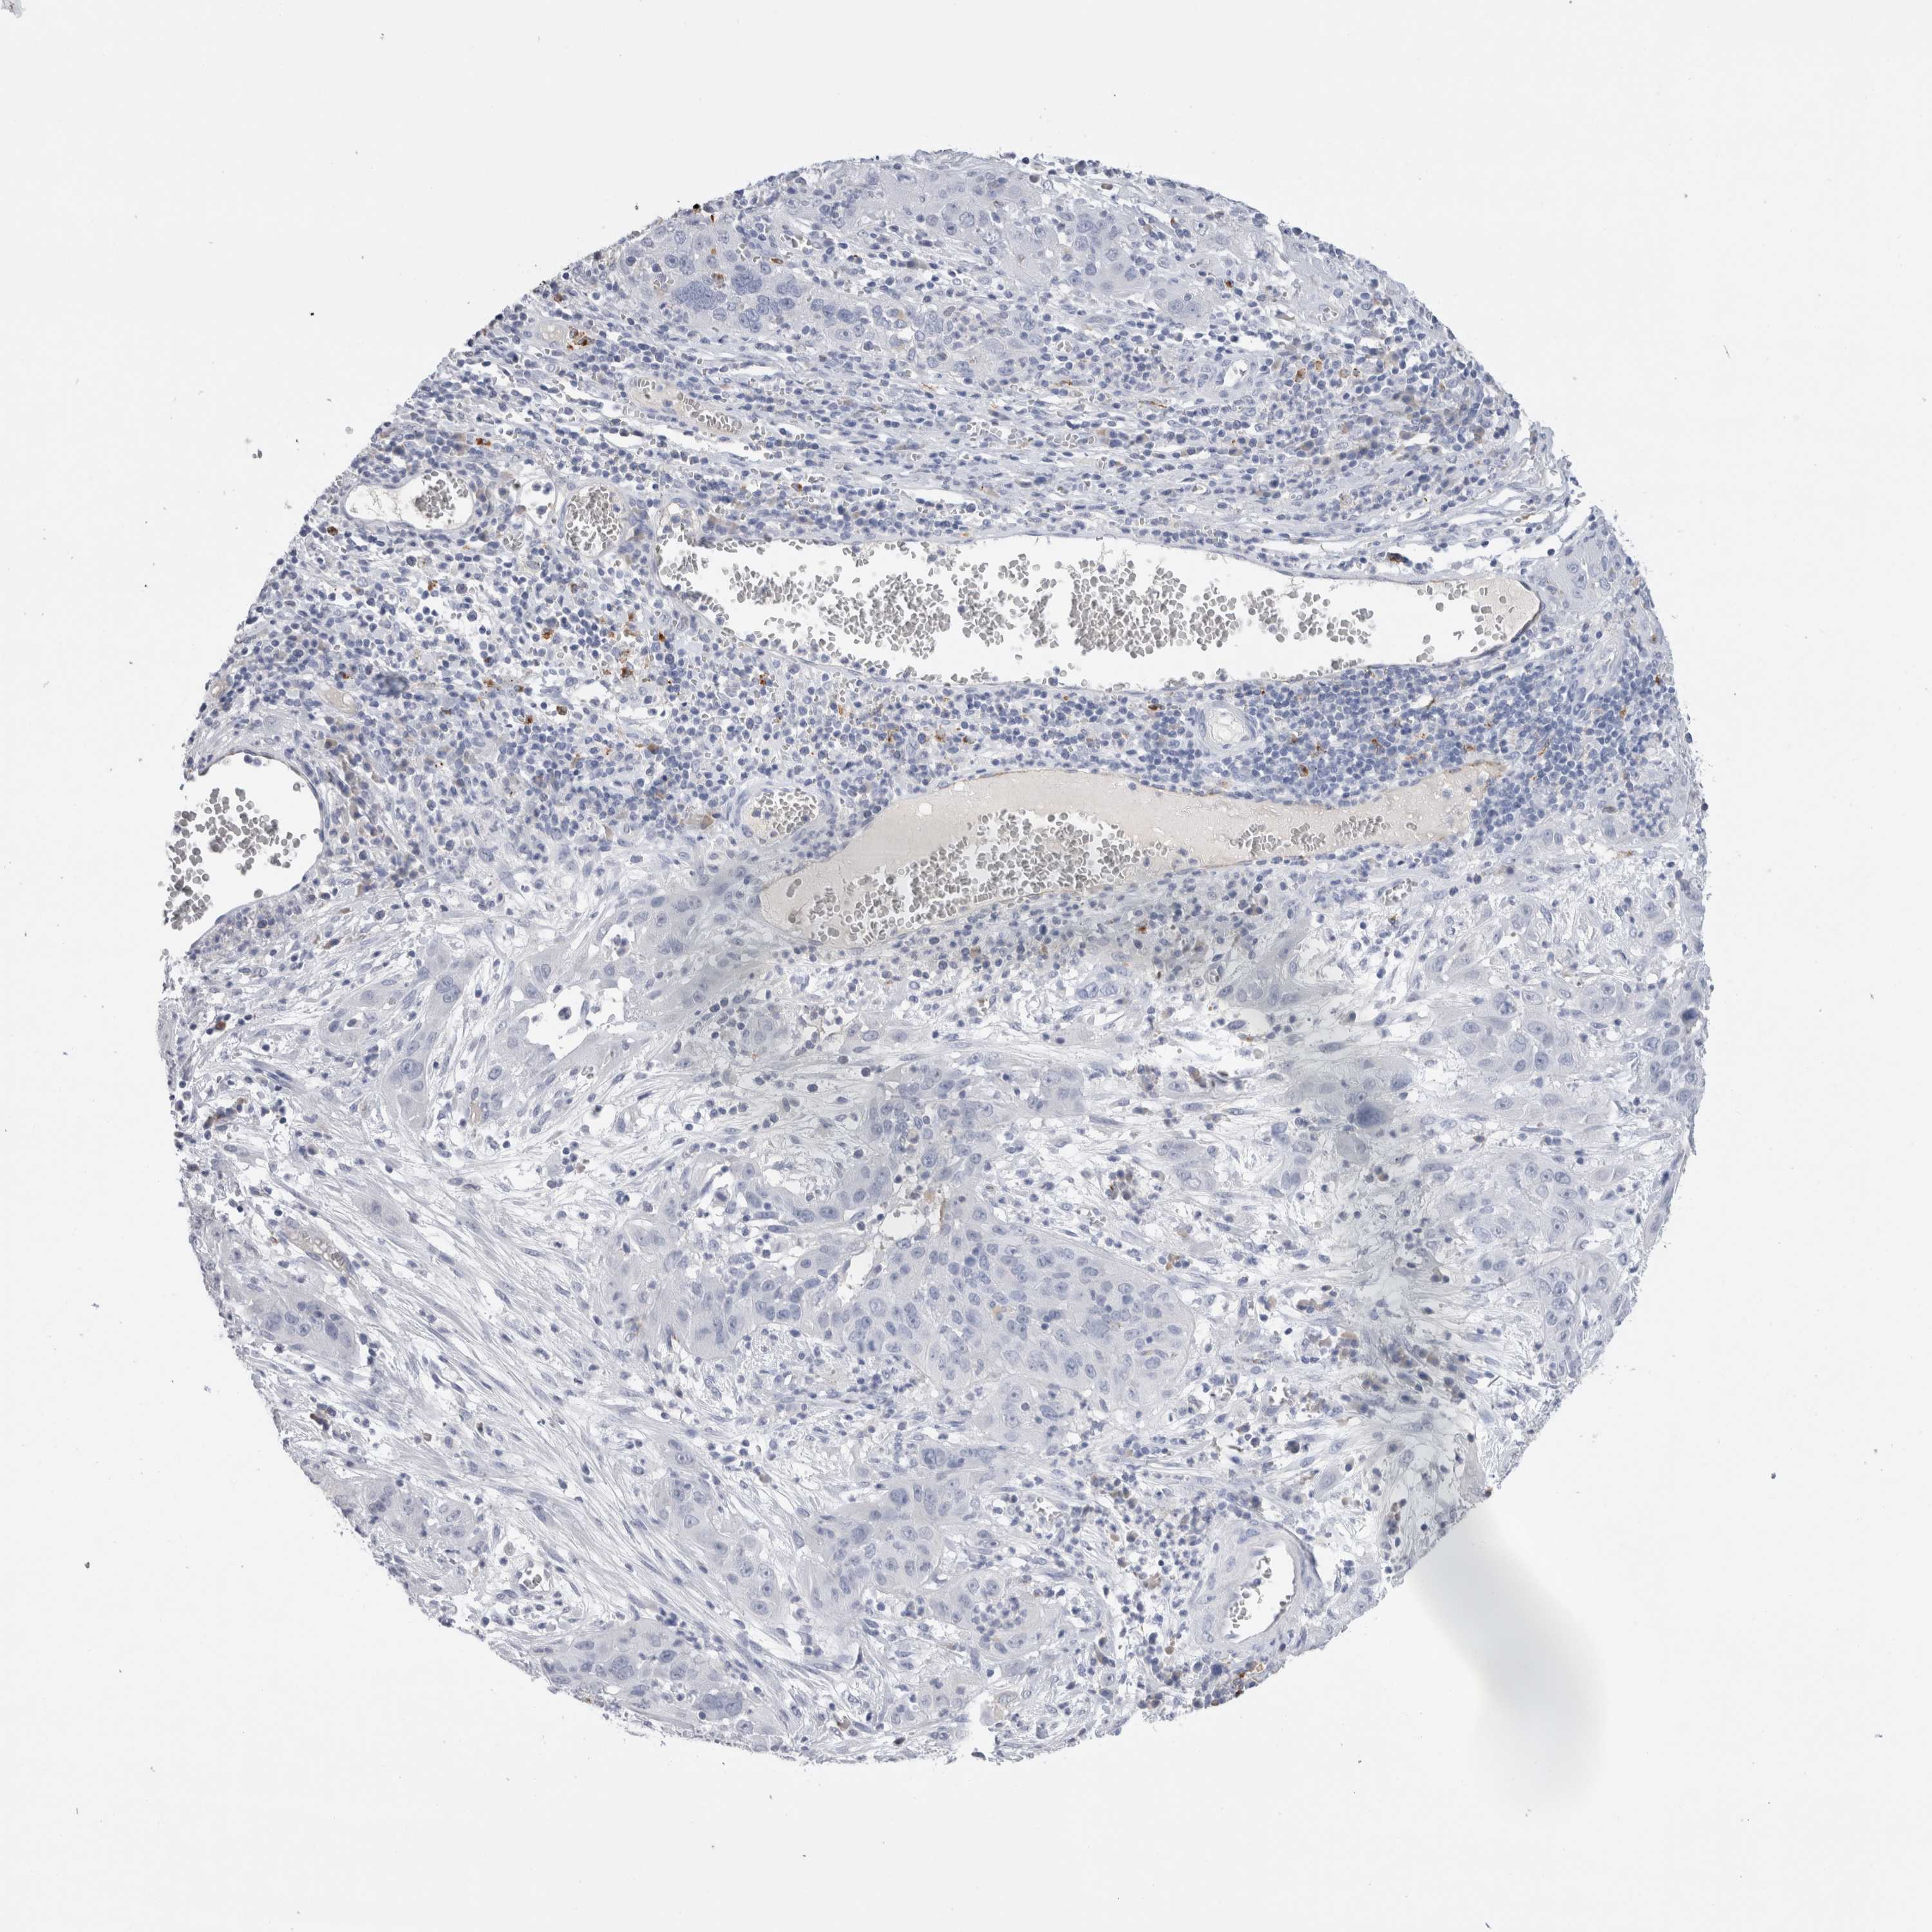

CERVICAL CANCER - Protein expressioni

A mouse-over function shows sample information and annotation data. Click on an image to view it in a full screen mode. Samples can be filtered based on level of antibody staining by selecting one or several of the following categories: high, medium, low and not detected. The assay and annotation is described here.

Note that samples used for immunohistochemistry by the Human Protein Atlas do not correspond to samples in the TCGA dataset.

Antibody stainingi

Antibody staining in the annotated cell types in the current human tissue is reported as not detected, low, medium, or high, based on conventional immunohistochemistry profiling in selected tissues. This score is based on the combination of the staining intensity and fraction of stained cells.

Each image is clickable and will lead to virtual microscopy that enables deeper exploration of all samples and also displays staining intensity scores, fraction scores and subcellular localization as well as patient and tissue information for each sample.

Antibody HPA051467

Antibody CAB025133

Squamous cell carcinoma, NOS

Adenocarcinoma, NOS